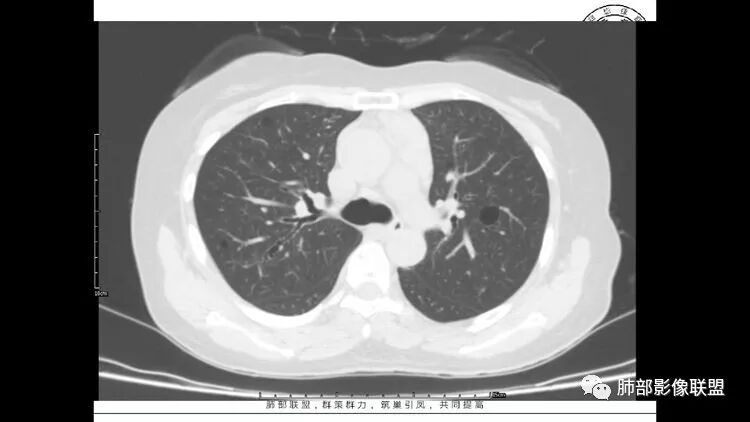

胸CT:1.双肺多发囊性变,以中下肺为主,病变边缘可见肺动脉,部分囊内可见分隔及肺动脉,双下部分肺野周围可见小叶中心结节及树丫征。

3.纵隔淋巴结肿大?,以主动脉弓为界向上向下增大。

多发气囊,气囊内可见血管进入,因患者眼干伴类风湿,可能有干燥综合征,那LIP可能性大。因为不是育龄期发病,可排除LAM。患者左纵膈淋巴结肿大,且有融合趋势,结合左下肺病灶,考虑合并恶性肿瘤,淋巴瘤?鉴别结节病

双肺多发囊腔伴结节 部分结节周围有晕 边缘清 前纵隔多发淋巴结增大 考虑lip伴淋巴瘤?

老年女性,长期使用激素史。双肺多发散在斑片状磨玻璃密度影及大小不等的薄壁含气囊腔,下肺相对较多较大。双肺多发结节,左肺上叶结节相对较大,界清,边缘光滑,分叶不明显。右肺下叶前外底段散在树丫。前上纵膈偏左侧不规则软组织团块,颗粒感,偏软。肺内囊腔及磨玻璃影考虑淋巴细胞间质性肺炎,或淋巴管肌瘤病。纵膈团块考虑淋巴管瘤。两者结合,考虑淋巴细胞增生病变。右肺下叶散在树丫,结核待排。双肺结节性质待定。

双肺多发散在斑片状磨玻璃密度影及大小不等的薄壁含气囊腔,下肺相对较多较大。双肺多发结节,界清,边缘光滑,分叶不明显。右肺下叶前外基底段散在斑片树芽。前上纵膈偏左侧不规则软组织团块,密度不均,其内可见不规则纤维样低密度,周围簇状小淋巴结。考虑1淋巴细胞间质性肺炎。2考虑纵膈胸腺淋巴瘤。

前纵隔结节,附近小淋巴结

LIP影像重要线索一句话:

双肺下叶分布为主的间质改变(磨玻璃影、小叶间隔增厚)、散在气囊影(常有血管贴边)、边界不清小结节